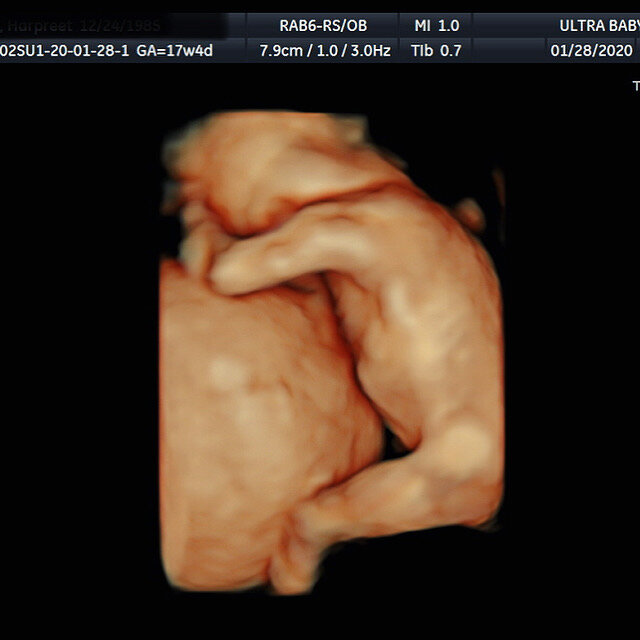

4D Examples